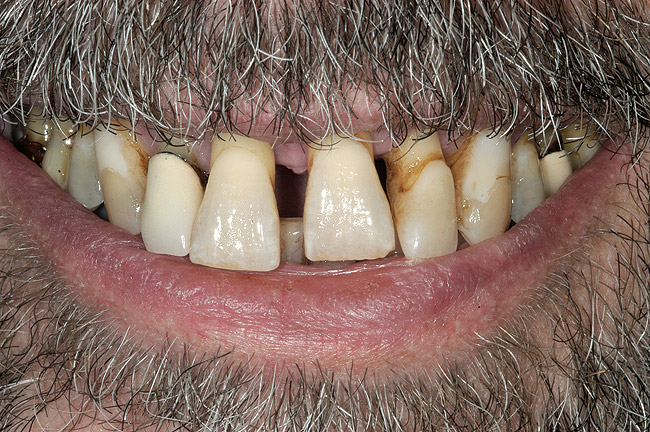

Un pacient în vârstă de 53 ani s-a prezentat cu îngrijorarea majoră privind aspectul, sensibilitatea şi mobilitatea dinţilor săi (fig. 1). El a răspuns pozitiv la chestionarul dentar referitor la sângerarea gingiei, dinţi dureroşi, sensibilitate la temperatură, gustul sau mirosul neplăcut al cavităţii orale, bruxism şi pierderea dinţilor.

La examinare s-au obiectivat: dinamică labială maxilară crescută, cu afişarea în repaus a 3-4mm din incisivi. La zâmbetul total, marginile gingivale libere nu erau vizibile, datorită recesiunii, dar 2-4mm din structura radiculară era vizibilă dincolo de joncţiunea smalţ-cement (CEJ) la toţi dinţii superiori. Festonul ţesutului moale era apropiat de normal, însă părea neatractiv datorită gradului mare de recesie şi a pierderii papilei. În regiunea frontală inferioară s-a remarcat asimetria orizontală (fig. 2).